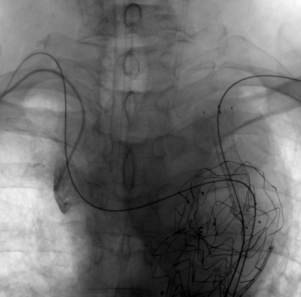

重建ARSA

按照同样的术式,将导丝超选进ARSA的内嵌分支开口后,置入Viabahn覆膜支架并释放。

治疗车怎么推【弓部重建直通车】梅州市人民医院心内科团队运用Castor®分支型支架联合预开窗技术治疗主动脉弓动脉瘤合并迷走右锁骨下动_https://www.jmylbn.com_新闻资讯_第15张

超选导丝进入ARSA

术后造影

术后造影显示,支架有效隔绝瘤腔,LCCA、LSA和ARSA血流供应通畅,支架无移位和内漏现象发生,手术圆满成功。